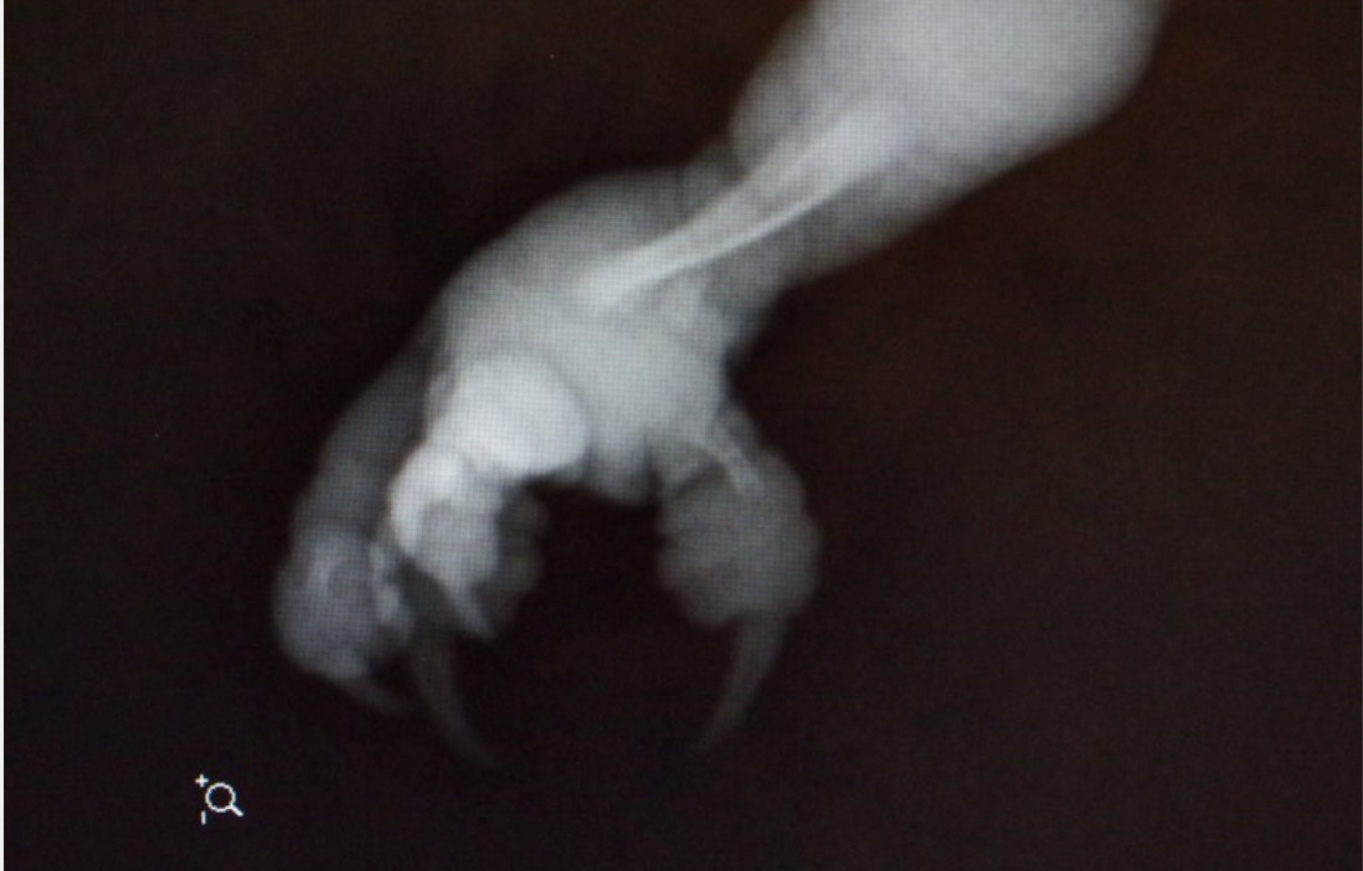

Po przyjeździe do kliniki CROW, Edytka została zbadana, wykonano zdjęcia RTG, aby ustalić, czy nie zostały złamane kości lub czy nie powstały wylewy wewnętrzne. Zdjęcia wskazują na to, że nie ma żadnych złamanych kości są natomiast oznaki odwodnienia i utrata masy ciała.

Z powodu obrzęku nogi, istnieją obawy o uszkodzenie nerwu ze względu na brak przepływu krwi. Więcej zostanie ustalone dzisiaj. Okaże się też, czy opuchlizna się zmniejszyła .

Zdjęcia CROW :